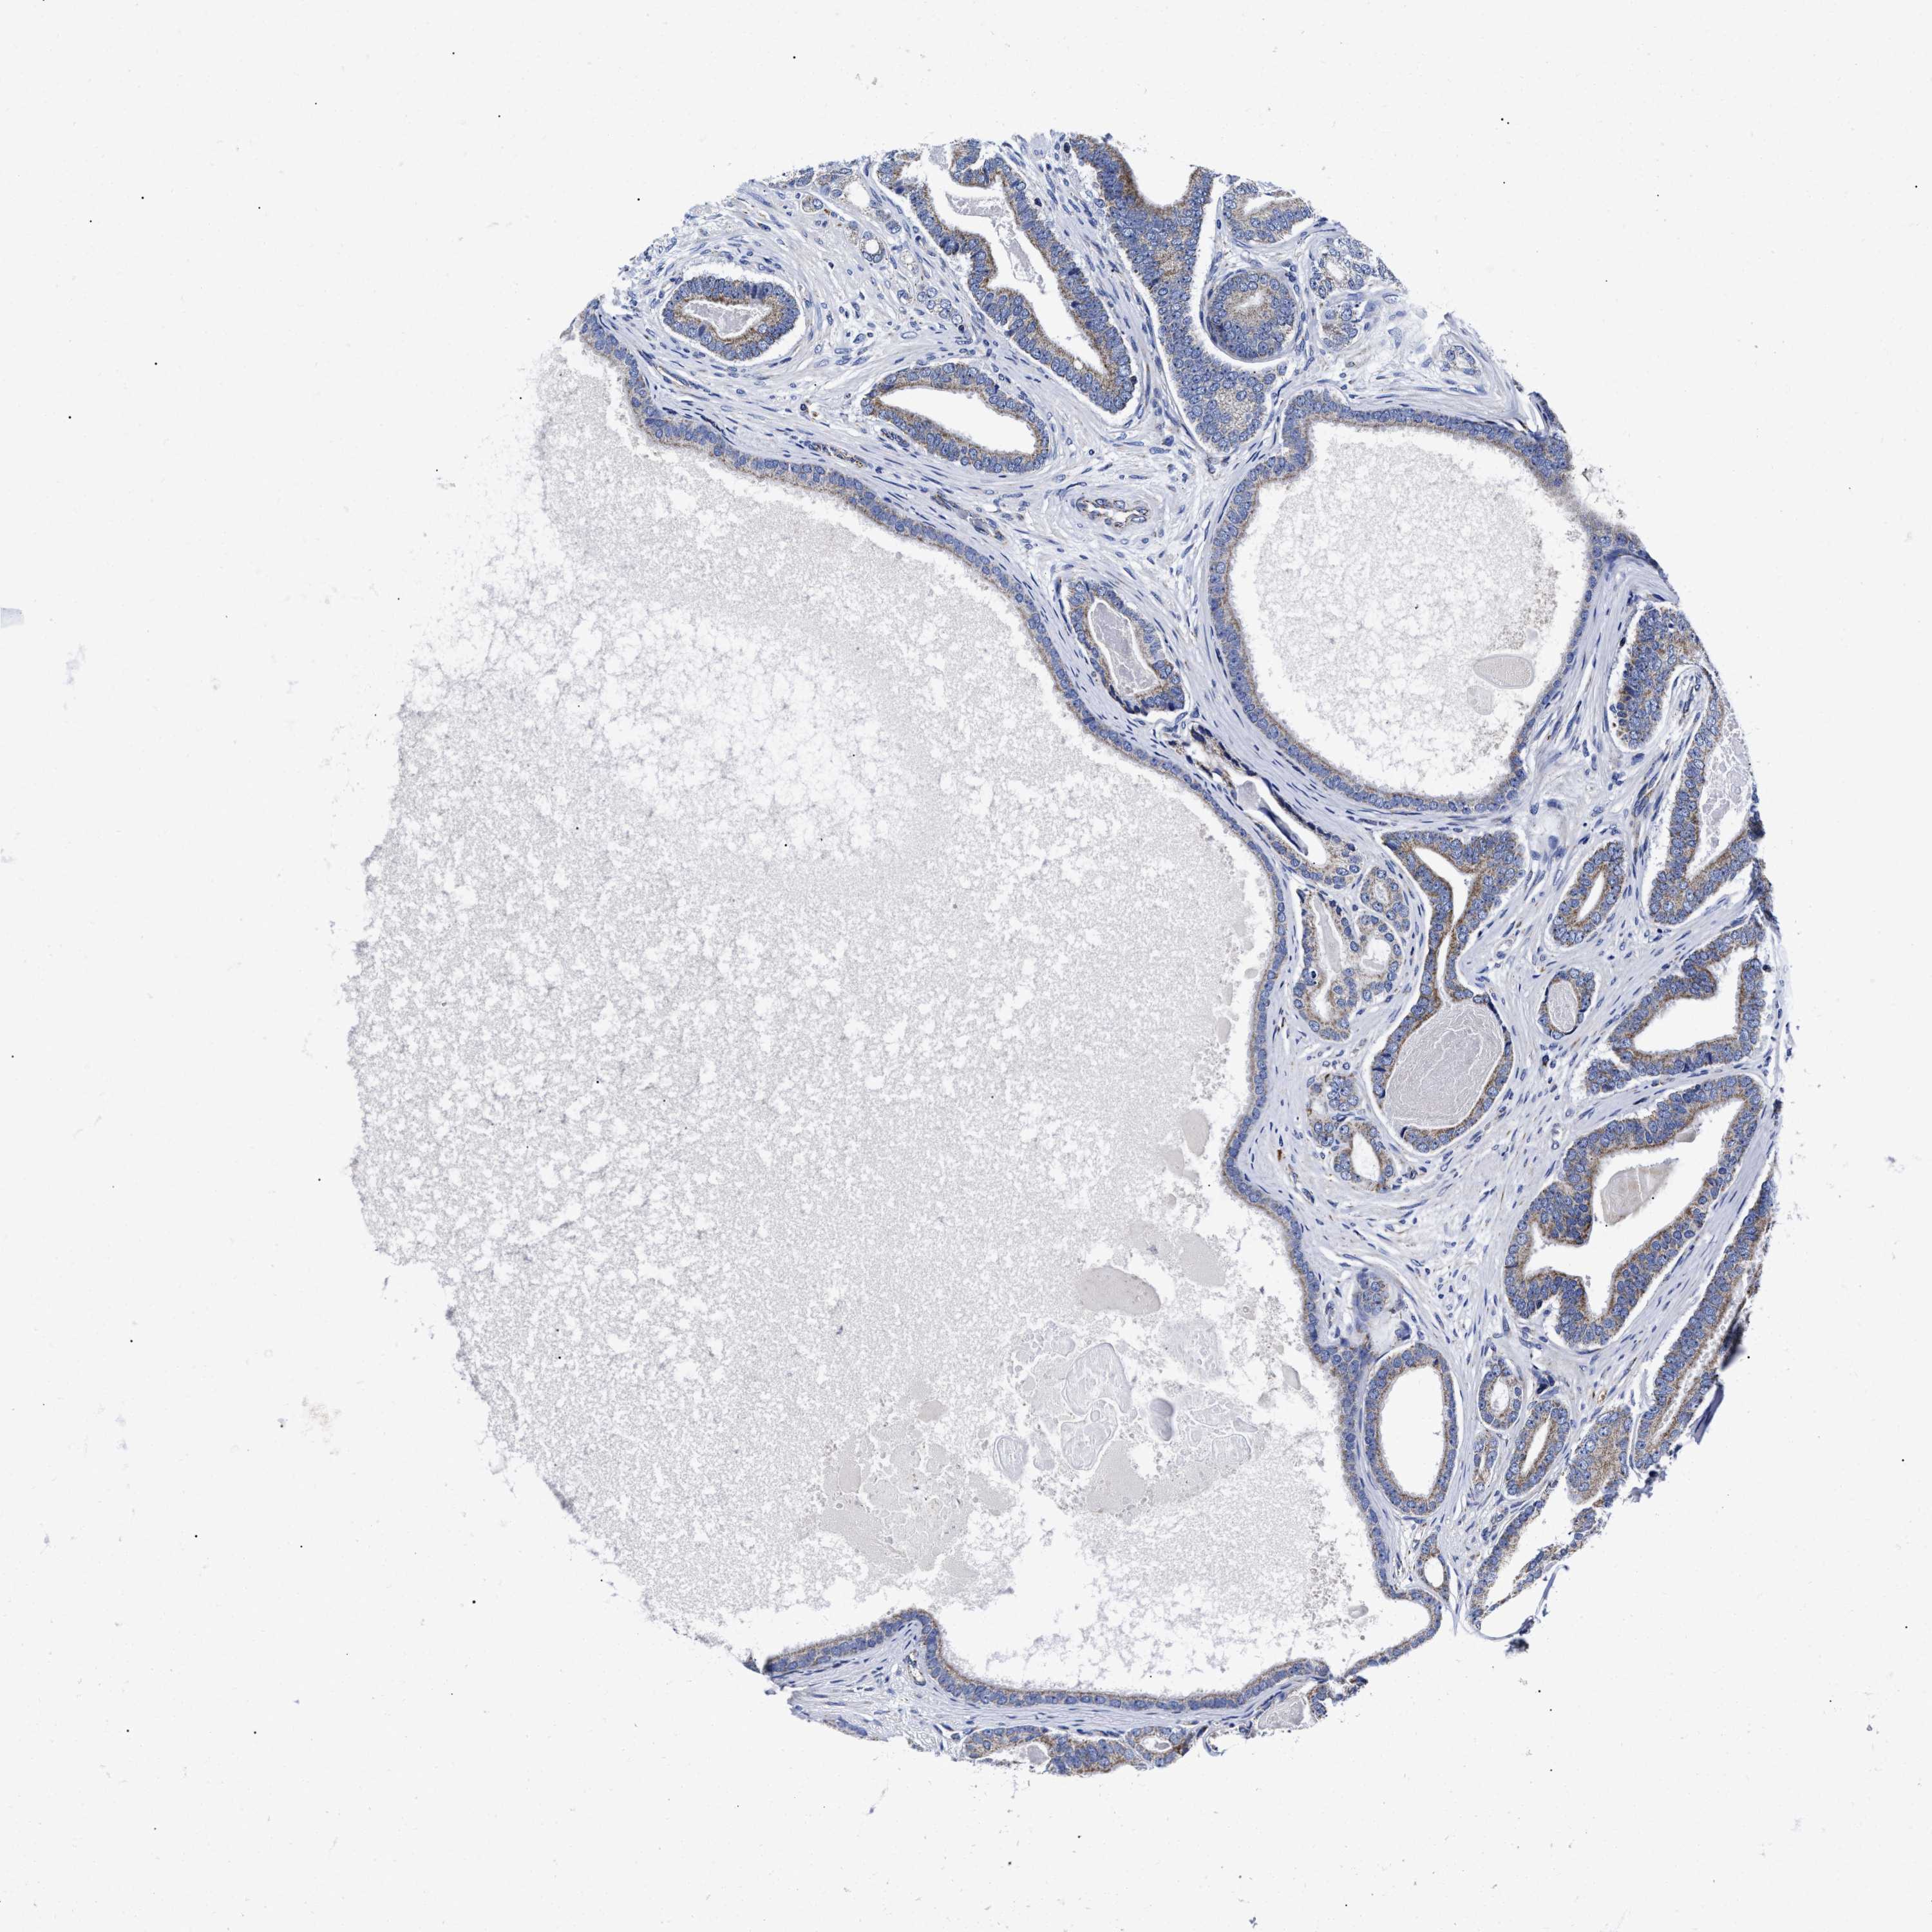

PROSTATE CANCER - Protein expressioni

A mouse-over function shows sample information and annotation data. Click on an image to view it in a full screen mode. Samples can be filtered based on level of antibody staining by selecting one or several of the following categories: high, medium, low and not detected. The assay and annotation is described here.

Note that samples used for immunohistochemistry by the Human Protein Atlas do not correspond to samples in the TCGA dataset.

Antibody stainingi

Antibody staining in the annotated cell types in the current human tissue is reported as not detected, low, medium, or high, based on conventional immunohistochemistry profiling in selected tissues. This score is based on the combination of the staining intensity and fraction of stained cells.

Each image is clickable and will lead to virtual microscopy that enables deeper exploration of all samples and also displays staining intensity scores, fraction scores and subcellular localization as well as patient and tissue information for each sample.

Antibody HPA020961

Antibody HPA059109

Staining

High

Medium

Low

Not detected

Intensity

Strong

Moderate

Weak

Negative

Quantity

>75%

75%-25%

<25%

None

Location

Nuclear

Cytoplasmic/membranous

Cytoplasmic/membranous,nuclear

Adenocarcinoma, High grade

Adenocarcinoma, Low grade